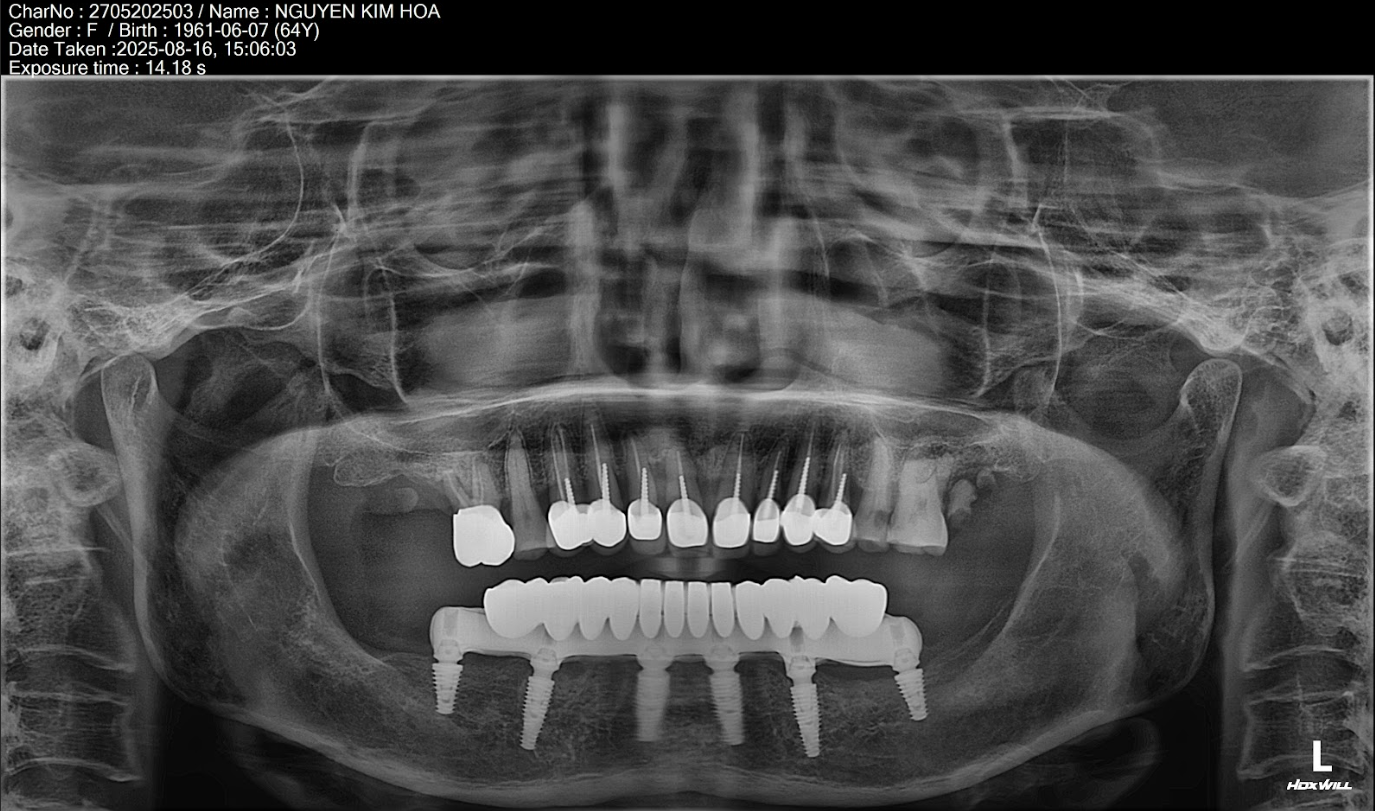

Trường hợp mất răng của cô Nguyễn Kim Hoa (64 tuổi; Hoàn Kiếm- Hà Nội); Trồng Implant toàn hàm dưới

Tình trạng:

01/06/2025: Cô Kim Hoa đến đến phòng khám gặp ThS BS Phạm Hùng Sơn với tình trạng răng:

*Hàm trên

+ Hàm trên tiêu xương nhiều

+ 2 răng số 7 hàm trên đều mất hết (R17, 27)

+ Toàn bộ cụm răng cửa từ răng số 4 bên trái sang bên phải 8 răng đều đã điều trị tủy cắm chốt

+ Răng số 6 hàm trên bên phải (R16) sâu to sát tủy

*Hàm dưới:

+ Hàm dưới tiêu xương nhiều

+ Răng số 5 bên trái (R35) và răng số 4 bên phải (R44) gãy chân

+ Răng số 5,6,7 hàm dưới bên phải (R45,46,47) mất

+ Răng số 6,7 hàm dưới bên trái (R37, 36) mất

Kế hoạch điều trị:

+ Chia thành 2 đợt điều trị cấy toàn hàm dưới trước

+ Trồng răng toàn hàm dưới 6 trụ Neodent của Thụy Sỹ: 22,5 Triệu x 6 = 135 Triệu

+ Làm hàm sứ rời Zirconia 12 răng: 54 Triệu

Tổng chi phí điều trị trồng răng toàn hàm trên: 135 Triệu + 54 triệu = 189 Triệu